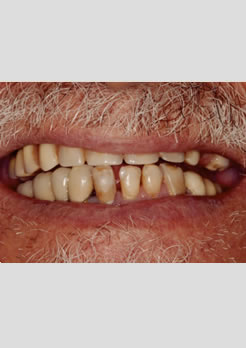

Paciente sexo masculino 62 anos, portando dentadura superior e vários dentes inferiores comprometidos. Foi indicado duas prótese fixas aparafusadas, na arcada supeior foram realizados 6 implantes e na arcada inferior 5 implantes.

Antes do tratamento